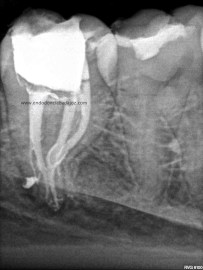

Sistemas de Conductos de un 4.7

Nos remiten a  la clínica una pieza 4.7, con necrosis pulpar y afectación periodontal, periodontitis apical:

La anatomía de los conductos nos hacia sospechar de un caso algo más complicado. Lo más complicado fue mantener la permeabilidad de los conductos. Instrumentamos con sistema rotatorio de Mtwo, mucha irrigación, se usó Irrisafe en los últimos lavajes, y como sistema de obturación usamos Condensación vertical con ola contínua, haciendo un backfilling con la Pistola Obtura II.

1. En los últimos lavajes??? hay Dr. Nieto cuántas influencias tiene usted.. Una vez más, hace que me enorgullezca tener un amigo así…eres un crack. cómo me gustaría saber que anatomía interna tiene este molar, y cuántas salidas tiene…hace donde irán esos conductos laterales presentes en los tres conductos? Qué difícil es manejar este caso, y lo importante que es no tener prisa por preparar el tercio apical en este tipo de curvaturas. Un abrazo…